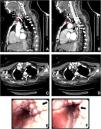

We describe a patient who underwent emergency tracheostotomy due to failed oro-tracheal intubation procedure for the anatomical conformation, during prolonged generalized non motor seizures with severe respiratory failure. CT scan shows multiple calcified nodules on the antero-lateral tracheal wall that spared the laryngeal tract (Fig. 1A–D), confirmed by bronchoscopy (Fig. 1E and F). Histological examination of a biopsy fragment sustained the diagnosis of TO.

In the antero-lateral tracheal wall, thorax CT scan shows calcified nodules, which protrude into the airway (A–D, red arrows). Large nodules, above the tracheal cannula cuff, are in contact with the cannula itself and occluding the tracheal lumen (B). Bronchoscopy reveals firm and glossy nodules with intact mucosa layer (E and F, black arrows), the posterior tracheal wall is spared.